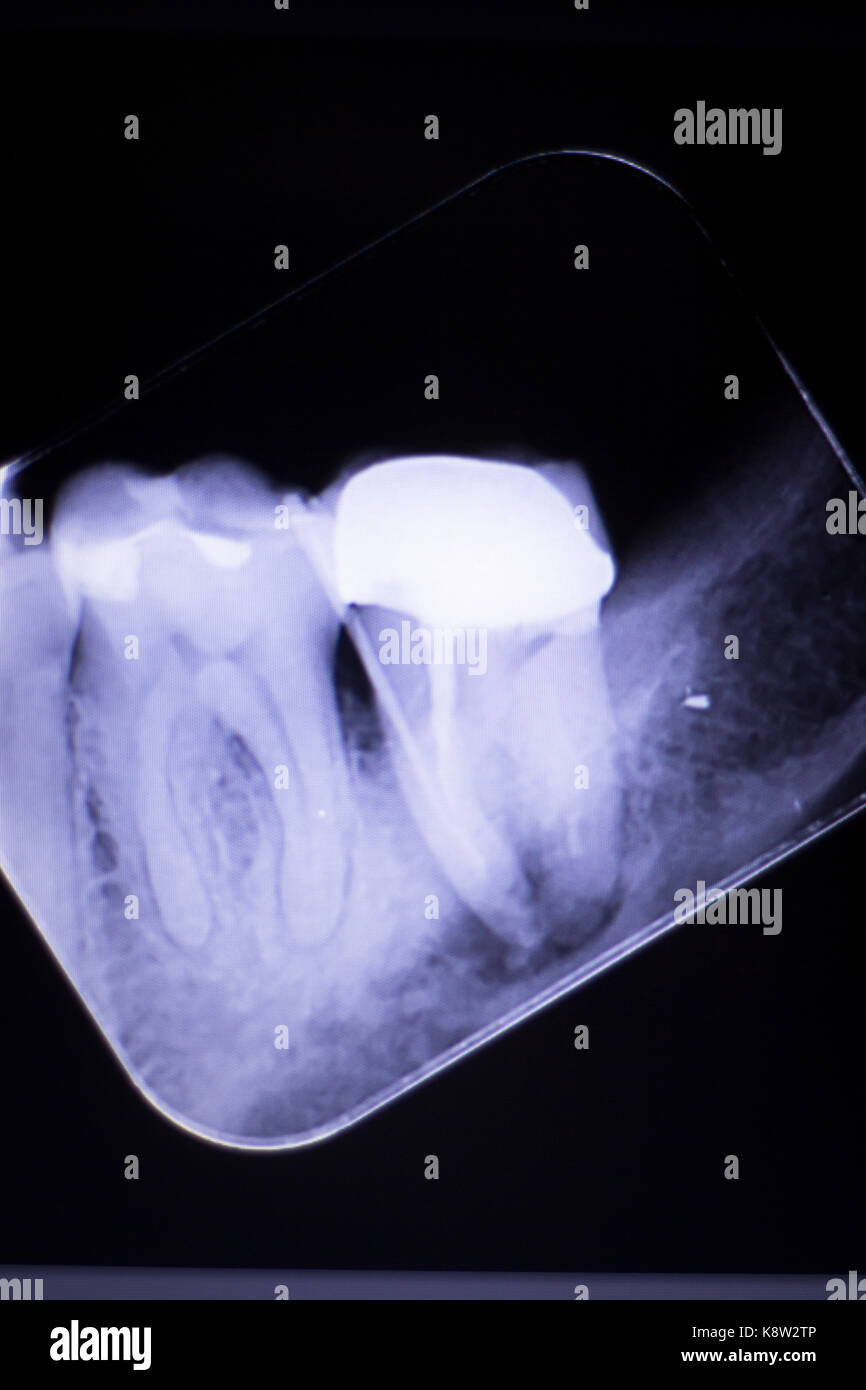

Dental xray test scan of tooth with crown filling and root canal

Dental xray test scan of tooth with crown filling and root canal X Ray Of Tooth With Filling Here is a picture of what a different tooth with decay underneath of an existing filling looks like. For example, under a filling, or between the teeth. There is no real explanation for it usually. The images produced can show the dentist or hygienist details that cannot be seen with the naked eye, such as cavities, bone loss, and impacted. X Ray Of Tooth With Filling.